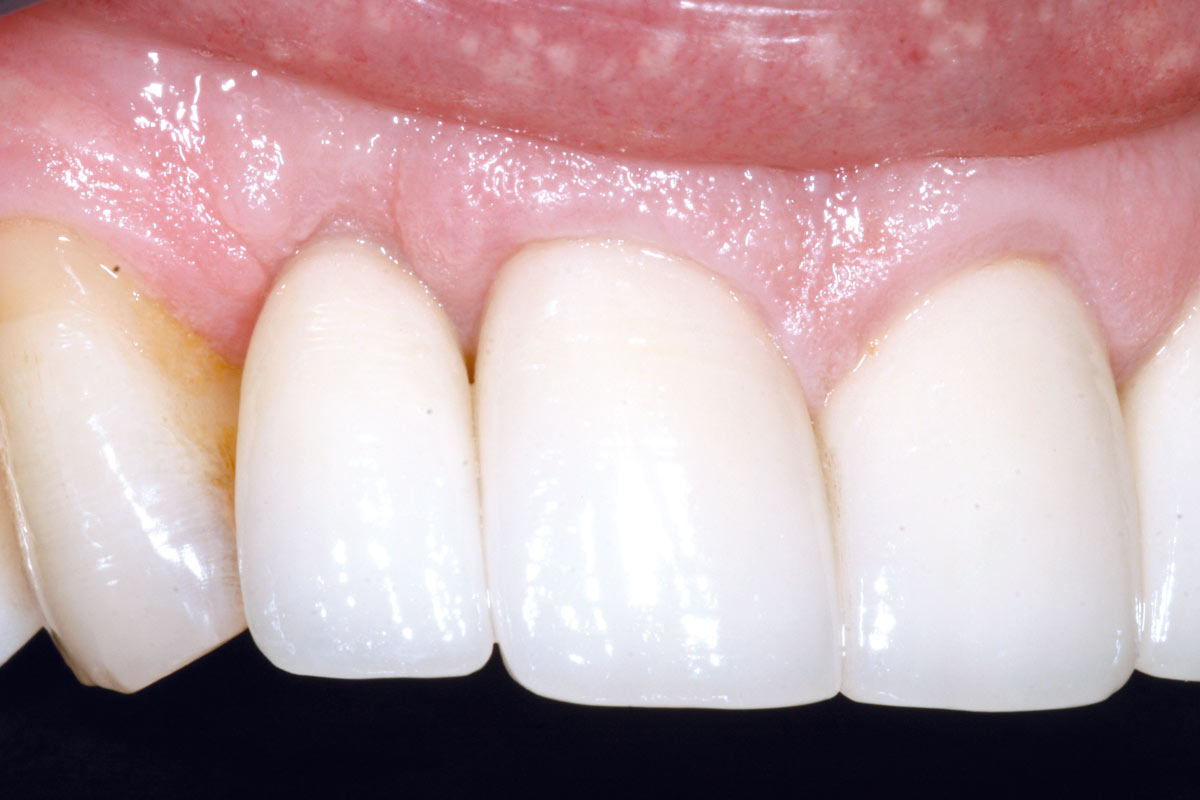

1/19 - Initial situation: Inflammated tooth #12Bone augementation with maxresorb® - Dr. R. Cutts

Initial situation: Inflammated tooth #12